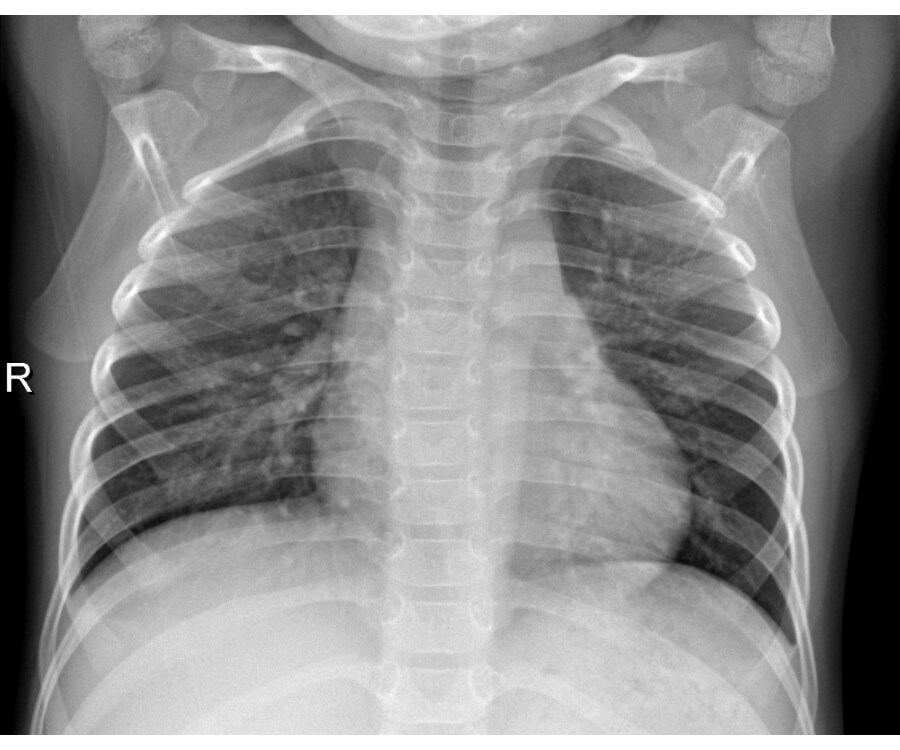

Chest radiograph of left upper lobe pneumonia diagnosed by a paediatric pulmonologist in a 12 month old. It is one of the leading causes.   chest radiography is the primary imaging study used to confirm the diagnosis of pneumonia.  neonatal pneumonia refers to inflammatory changes of the respiratory system caused by neonatal infection.   performing chest radiography on pediatric patients can be for a number of indications 1:   chest radiographs can show hazy opacities similar to those associated with sdd, coarse irregular opacities similar to those associated with.

Baby Chest Xray Pneumonia .   chest radiography is the primary imaging study used to confirm the diagnosis of pneumonia.   performing chest radiography on pediatric patients can be for a number of indications 1: Chest radiograph of left upper lobe pneumonia diagnosed by a paediatric pulmonologist in a 12 month old. It is one of the leading causes.  neonatal pneumonia refers to inflammatory changes of the respiratory system caused by neonatal infection.   chest radiographs can show hazy opacities similar to those associated with sdd, coarse irregular opacities similar to those associated with.